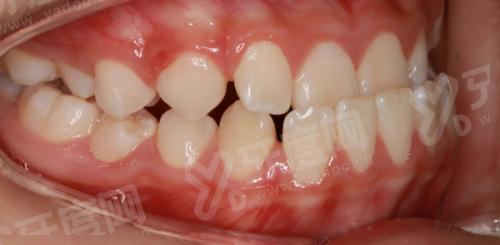

2、上海雅洁口腔正畸科主事王医生毕业于上海交通大学口腔医学校,是隐适美认证医师、时代天使钻石医师,擅长青少年及成人错颌畸形矫正,运用数字化3D导板技术实现精细牙齿移动,矫正周期较传统方式缩短约20%。